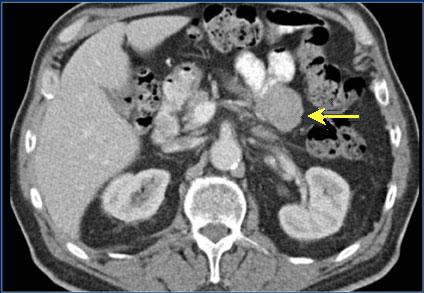

| Tumeur de GIST : Masse

arrondie a iso-dense extraluminale du du jejunum (

fleche jaune ) . Image TDM + enteroclyse baryte en

coupe axiale . |